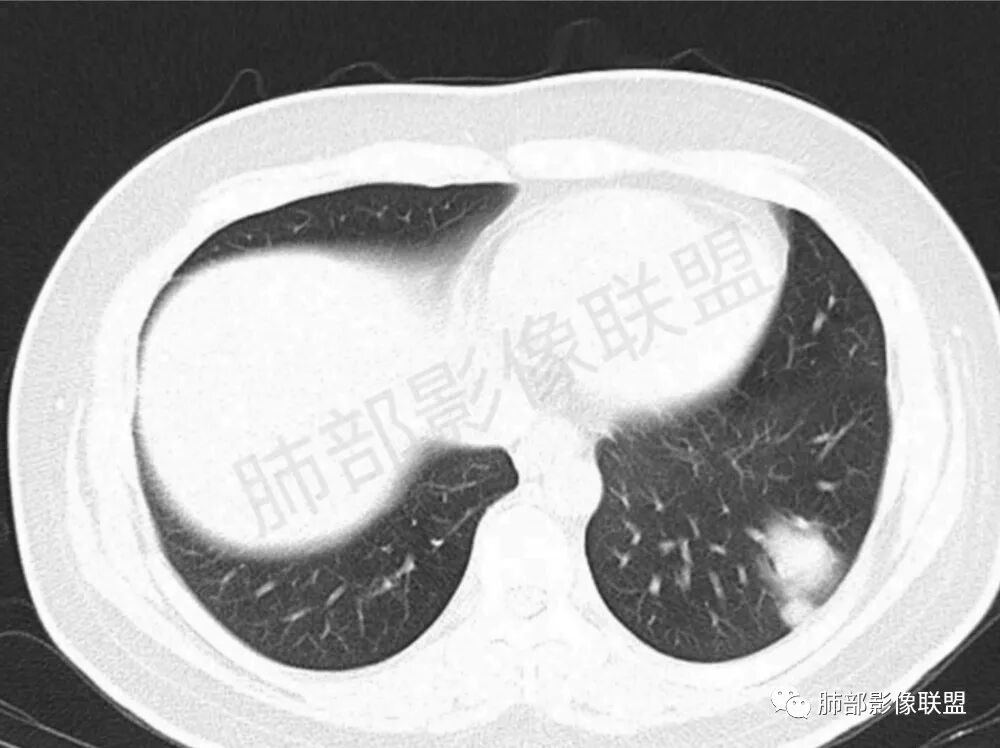

男性,22岁,HIV病史,症状半年,双肺多发大小不等结节影,边缘光滑,密度均匀,以胸膜下分布为主,部分与胸膜相连,胸膜下脂肪间隙可见,病灶近段支气管走行病灶内,远端似有堵塞,无增强图像,考虑隐球菌,鉴别:淋巴瘤,GPA

双肺多发结节影,膨隆,边缘光滑,圆顿,沿支气管血管束分布为主,部分贴胸膜,部分见空洞,空气支气管征

两肺多发结节性,大部分位于胸膜下,部分结节周围可见晕征。局部结节内可见扩张的支气管,纵隔淋巴结大,脾大,22岁男,HIV阳性,常规先考虑隐球菌。鉴别淋巴瘤,结核,马儿。

男,22,半年前咳嗽伴少痰,查HIV阳性,痰查TB阳性,既往有肺部斑片影伴空洞、纵隔淋巴结肿大、脾大。SCC、CA50、CA199、FER增高,此次胸部CT:两肺多发结节影,部分沿血管束分布,部分贴胸膜下,大小不一,密度不一,部分较散、边缘模糊,部分较实、圆钝、周围模糊晕,部分结节有支气管进入穿行自然,部分结节有血管分支自如通过。考虑HI∨相关淋巴增殖类病变,淋巴瘤?LYG?鉴别PC、TB。

青年男性,半年前咳嗽,HIV阳性,结核DNA阳性,肿标糖类抗原和铁蛋白增高。外院影像有纵隔淋巴结增大伴脾大,肺部病灶空洞。现在影像:肺内多发沿支气管分布(有支气管充气征,长轴沿支气管分布)及胸膜下分布(平行于胸膜)的大小不等结节,个别伴有空洞,双侧腋窝淋巴结肿大。纵隔图片不够,是否还有淋巴结肿大未知,脾脏未显示。

1.双肺多发大小不一结节,外围为主,边界尚清,部分周围似有GGO

2.类圆形,部分与胸膜相连,糊墙

3.支气管通畅或近端堵塞

空洞  游走  多变  支气管血管束分布,好符合啊

影像学缺乏特征性,以支气管血管周围、胸膜下及双肺下叶周边多发结节影最多见,结节易坏死形成空洞,伴有游走性和多变性的特征,结节周围可有磨玻璃样晕征,有时也可见单发结节影、薄壁的囊状阴影或弥漫性浸润影。肺门、纵隔淋巴结肿大少见, 可见胸腔积液和气胸。

肿块型∶表现为两肺多发大小不等的不规则肿块,肿块边缘不光整、欠锐利,有大的分叶,毛刺少见,增强扫描呈明显强化,可合并坏死、空洞;

结节型∶表现为两肺多发大小不等的结节,以两肺中下野多见,结节边缘欠锐利;